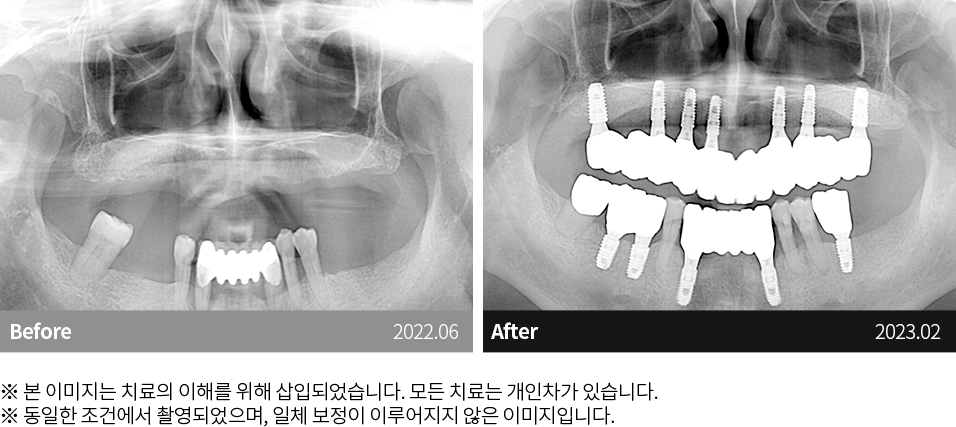

자연치아 보존원칙

고난이도케이스 치료

임플란트